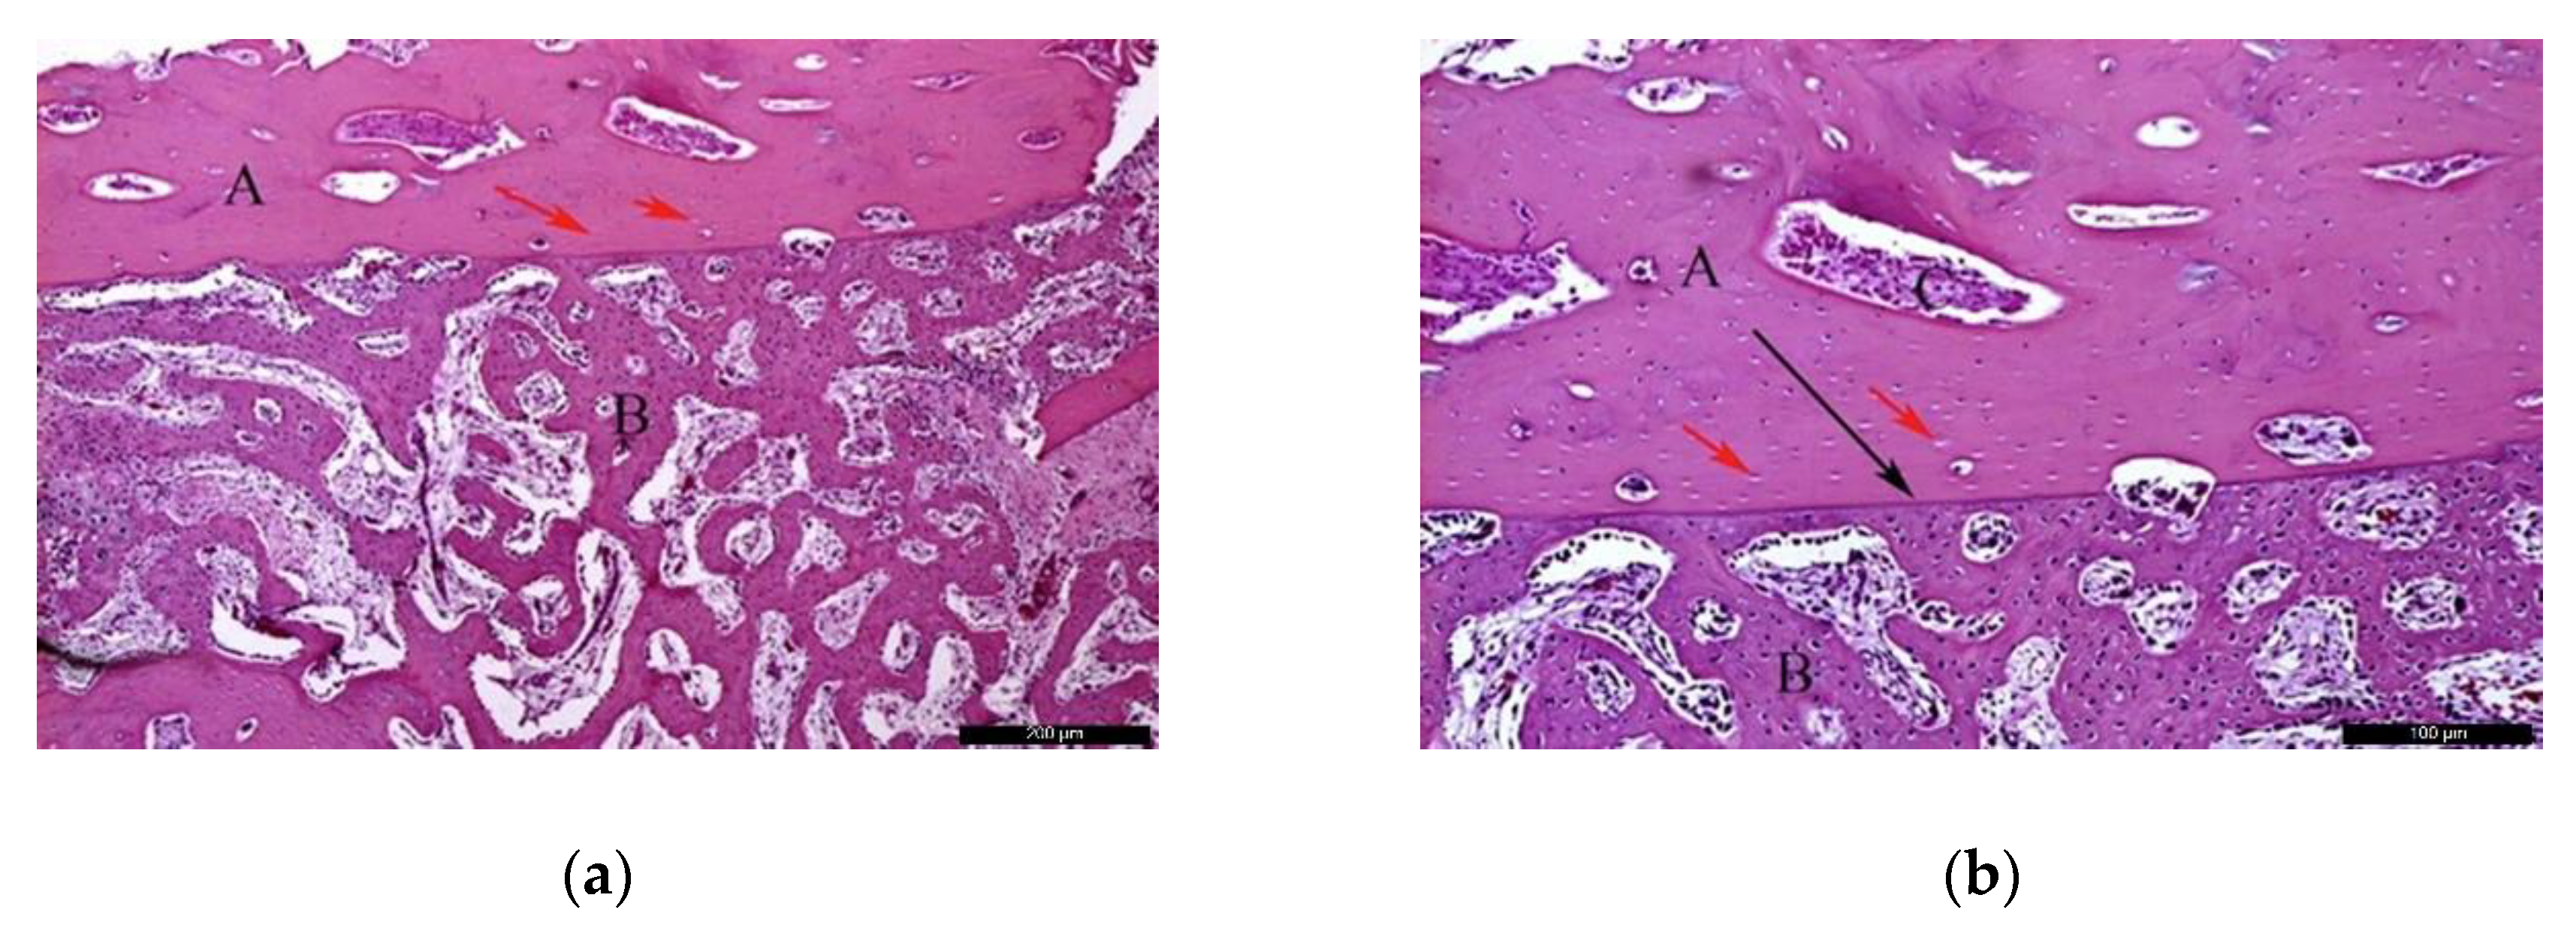

- Biomaterial group

In the BG, after 30 healing days (Figure 5a), it was possible to observe the biomaterial (A) in close contact with the newly formed bone (B), and the residual recipient site (C). In the surrounding areas of the neoformed bone, it was possible to identify a high number of lining cells compatible with osteoblasts (blue arrows) suggesting a phase of matrix synthesis. At higher magnification (Figure 5b), the contiguous contact between the biomaterial (A) and the neoformed bone (B) was appreciated. Lining osteoblast cells were identified in the periphery of the newly formed bone (blue arrows).

Figure 5.

Histological analysis of the biomaterial group (BG) at 30 days. (a) Biomaterial (A) in close contact with the newly formed bone (B), and the residual recipient site (C); osteoblast-like lining cells are indicated with blue arrows. Hematoxylin and eosin stain at a magnification 40×; (b) Biomaterial (A), newly formed bone (B), and lining osteoblast cells in the periphery of the newly formed bone (blue arrows). Hematoxylin and eosin stain at a magnification 125×.

In the BG, after 60 post-operative days (Figure 6a), the biomaterial (A) was enwrapped by neoformed bone (B). In the inner part of the biomaterial, it was possible to observe islands of newly formed bone, highlighting the osteoconductivity capability of the bone substitute. At the same time, areas of resorption associated with volume loss were noticed, indicating high solubility of the biomaterial. At higher magnification (Figure 6b), it was possible to observe the bone substitute (A) on the recipient bed (B), and neoformed bone tissue (C).

Figure 6.

Histological analysis of the BG at 60 days. (a) Biomaterial (A) enwrapped by newly formed bone (B). Hematoxylin and eosin stain at a magnification 40×; (b) Biomaterial (A) on the recipient bed (B), and newly formed bone (C). Hematoxylin and eosin stain at a magnification 125×.